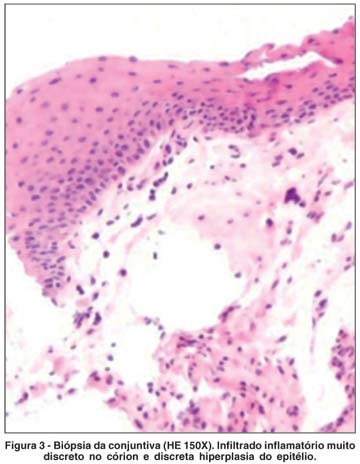

Foi solicitada avaliação dermatológica que sugeriu diagnóstico de LP. A biópsia das lesões de couro cabeludo (Figura 2) e mucosa oral confirmaram tal diagnóstico. Foi realizada biópsia conjuntival (Figura 3) com imunofluorescência direta (Figura 4), que revelou achados compatíveis com LP. Os fragmentos para análise histológica foram fixados em formol a 10% e processados para inclusão em parafina. Os cortes histológicos na espessura de 5 micrômetros foram corados com hematoxilina-eosina (HE). Os fragmentos para imunofluorescência (IF) foram imediatamente colocados em soro fisiológico gelado e em seguida congelados em criostato para realização dos cortes histológicos na espessura de 5 micrômetros, que foram incubados com os seguintes anticorpos (todos marca Dako) diluídos em solução salina tamponada (tampão PBS pH 7,4) com Azul de Evans 0,06%.

As características histopatológicas do LP na conjuntiva são menos documentadas do que as da pele. Neumann(13) sugeriu que as características principais seriam espessamento e duplicação da lâmina basal subepitelial e ausência de imunoglobulinas e C3 na zona da membrana basal. Um achado interessante do presente caso, também relatado em estudo anterior(10), foi a ausência de imunoglobulinas associada à presença de depósito de fibrinogênio na membrana basal à ID, associação esta que apesar de inespecífica, poderá constituir dado importante para o diagnóstico de envolvimento ocular pelo LP.